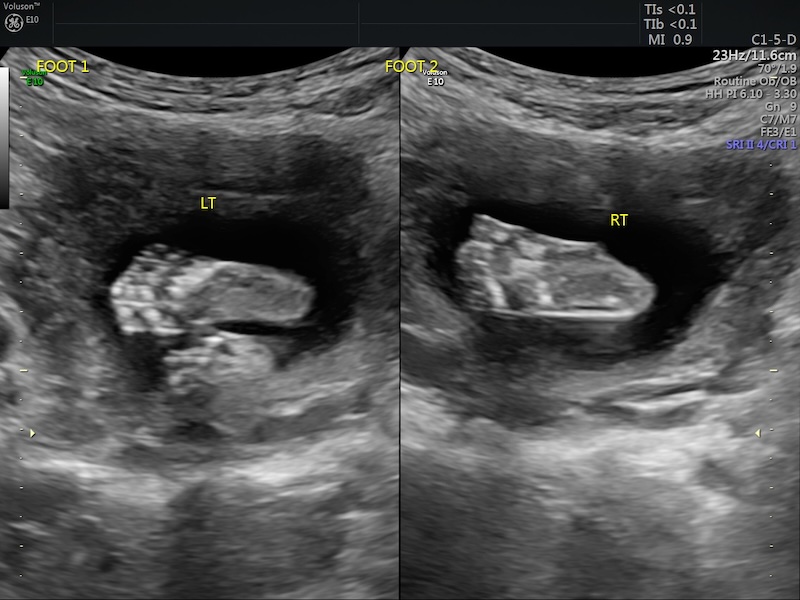

We made it to 20 weeks. What in the world! We had our anatomy scan and praise God, everything was measuring right on track!

This was Jimmy’s first time seeing the baby on an ultrasound and it was so fun to go to an appointment together! We have finally decided on a name(!), so that feels great. Two things of note from the anatomy scan were that she was in the breech (head up) position and my placenta was anterior.

I’m not too worried about the baby being breech at 20 weeks because she has a lot of time and room to flip head-down. And also, if she decides to stay breech? Okay, we’ll deal with that when the time comes! I’m just taking the pregnancy day by day and trusting in God and surrendering full control to Him. Because I’m definitely not the one in control!

The anterior placenta (which means the placenta is in the front instead of back) explains why I wasn’t feeling kicks until just around 20 weeks! I had a feeling that was the case. I’m glad to be feeling kicks now 🙂